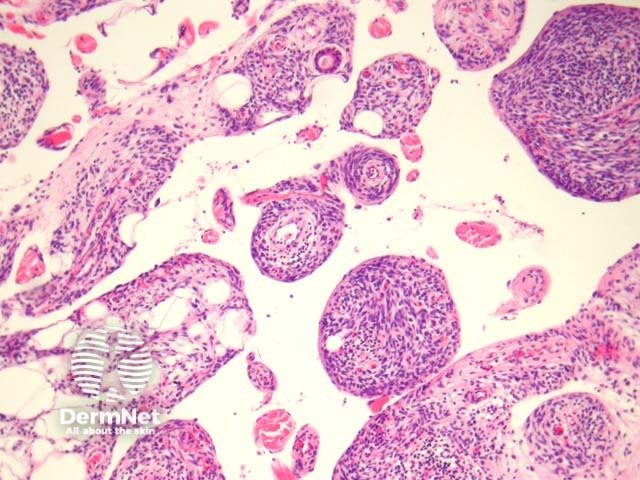

Unusually, spindle cell lipoma may exhibit a pseudoangiomatous morphology (figures 5, 6). Despite the unusual irregular clefts and soft tissue projections, the lesional cells themselves display the classic morphology of uniform cells with an elongated nucleus and bipolar cytoplasmic processes. Intermixed mature adipocytes are also usually seen.

Figure 5

Figure 6